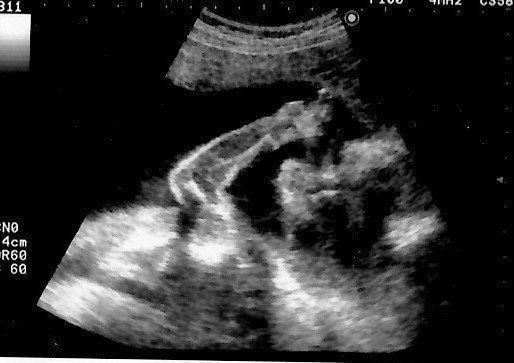

マダムまかろんさんの妊娠23週目のエコー写真 性別がほぼ確定

「性別は知りたいですか?」エコー画像を見ていた医師から問われて、「はい」と即答した私。しかし、告げられた性別は私が希望していたものではありませんでした。その日から数日間はかなり落ち込み、友人につい愚痴ってしまったほど。「赤ちゃんもおなかの中で聞いているよ。そんなこと言わないで」と友人からたしなめられ、ようやく我に帰りました。子どもを授かっただけでもうれしかった頃の気持ちを思い出して反省しました。